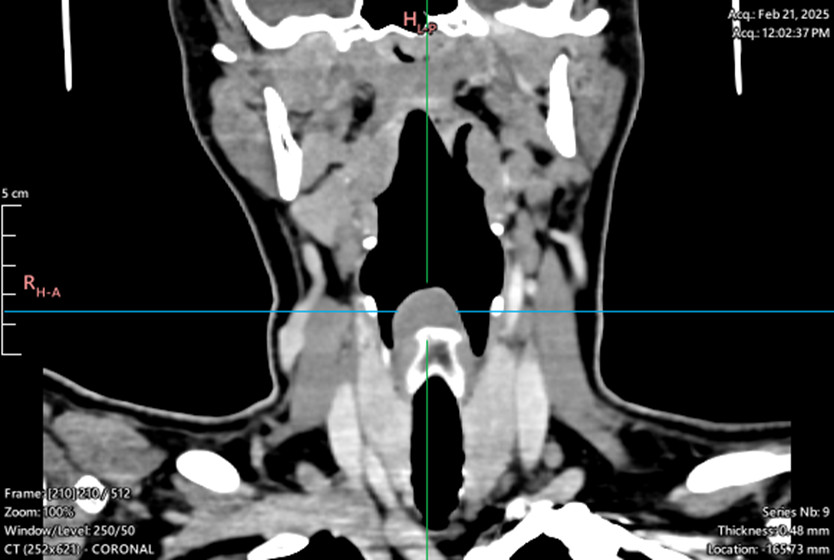

Patient No 2.

Laryngeal tumor - posterior commissure

Biopsy, granular cell tumor, granular cell myoblastoma, Abrikossoff tumor/div>

Symptoms: hoarseness, sensation of a foreign body in the throat, dysphagia